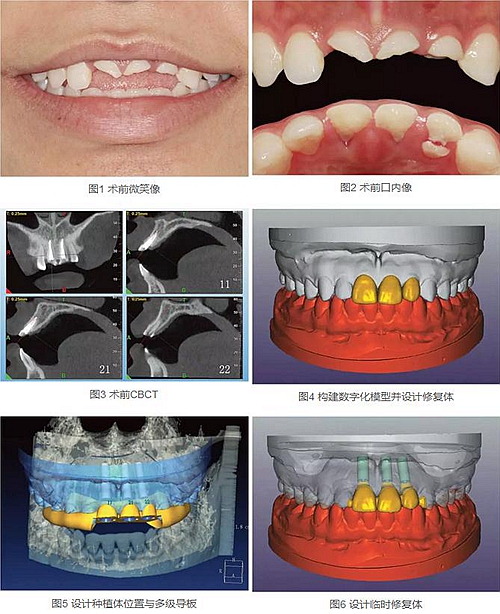

23歲女性患者,外傷導(dǎo)致上前牙折斷3天。檢查:中微笑線;上頜右側(cè)中切牙至左側(cè)側(cè)切牙殘根,不松動(dòng),腭側(cè)缺損達(dá)齦下5mm,牙齦中等厚度,齦緣基本完好。CBCT顯示:根長(zhǎng)約11mm,牙根長(zhǎng)軸與牙槽突方向基本一致,唇側(cè)骨板完好、厚度1.0mm,可用骨高度21mm。全身情況良好。

拍攝臨床照片、拍攝輕開口位CBCT(NewTom)、取聚醚印模灌制超硬石膏模型。

構(gòu)建數(shù)字化模型并設(shè)計(jì)修復(fù)體:將超硬石膏模型在口外掃描(Identica Hybrid),獲取軟硬組織表面形態(tài),構(gòu)建數(shù)字化模型,確認(rèn)咬合情況。根據(jù)天然牙殘根頸部形態(tài)設(shè)計(jì)修復(fù)體頸部形態(tài),使修復(fù)體頸緣輪廓與原有天然牙一致;按正常牙弓弧度與覆、覆蓋關(guān)系,結(jié)合紅白美學(xué)等原則確定修復(fù)體的三維形態(tài)。最后,導(dǎo)入患者面部照片,確認(rèn)模擬修復(fù)效果。

設(shè)計(jì)種植體位置并制作多級(jí)導(dǎo)板:利用Segma設(shè)計(jì)軟件,將CBCT數(shù)據(jù)和模型掃描數(shù)據(jù)進(jìn)行配準(zhǔn),調(diào)入模擬修復(fù)效果數(shù)據(jù),以修復(fù)為導(dǎo)向設(shè)計(jì)種植方案,設(shè)計(jì)種植體螺絲孔開口從修復(fù)體舌窩處穿出,最終實(shí)現(xiàn)螺絲固位的一體化基臺(tái)冠修復(fù)。根據(jù)種植體信息設(shè)計(jì)多級(jí)導(dǎo)板,參考修復(fù)體形態(tài)設(shè)計(jì)導(dǎo)板植入?yún)^(qū)頸緣外形,打印生成種植導(dǎo)板(Segma),并安裝金屬引導(dǎo)環(huán)。

設(shè)計(jì)并制作臨時(shí)修復(fù)體:如前所述,按照美學(xué)效果和咬合關(guān)系設(shè)計(jì)臨時(shí)冠外形,頸部形態(tài)與模型齦緣輪廓一致,保證臨時(shí)修復(fù)體在術(shù)后可以封閉拔牙窩。3顆臨時(shí)冠為連冠,齦外展隙適當(dāng)加大,為術(shù)后軟組織生長(zhǎng)提供一定的空間。在臨時(shí)冠近兩側(cè)鄰牙的切角處預(yù)留翼板,保證臨時(shí)冠戴入時(shí)可以找到準(zhǔn)確的位置。以銑削的方式加工臨時(shí)冠(Segma),待種植體植入后將其在口內(nèi)粘接于臨時(shí)基臺(tái)上。